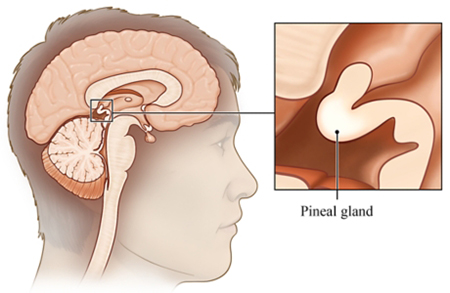

غده صنوبری که به عنوان غده کاجی یا غده پینهآل نیز شناخته می شود، یک غده درون ریز کوچک است که در مرکز مغز قرار دارد. غده صنوبری علیرغم اندازه کوچکش، نقش مهمی در تنظیم فرآیندهای فیزیولوژیکی مختلف در بدن از جمله چرخه خواب و بیداری، خلق و خو و رشد جنسی دارد.

غده صنوبری به شکل مخروط کاج است و به اندازه یک نخود است و قطر آن تقریباً 8 میلی متر است. در اپیتالاموس، ناحیه ای از مغز که بین دو نیمکره قرار دارد و توسط تالاموس احاطه شده است، قرار دارد. غده صنوبری از پینهآلوسیتها تشکیل شده است که سلولهای تخصصی هستند که ملاتونین، هورمونی که چرخه خواب و بیداری را تنظیم میکند، تولید و ترشح میکنند.

غده صنوبری به دلیل ارتباط با تجربیات معنوی و عرفانی به عنوان غده پینهآل شناخته شده است. غده پینهآل مفهومی است که در بسیاری از فرهنگ ها و ادیان یافت می شود و اغلب با شهود، توانایی های روانی و روشنگری همراه است.